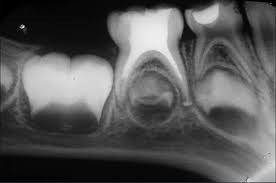

If the baby tooth is getting close to being pushed out by the adult tooth that replaces it, a Pulpectomy may not be advised. This can be judged by looking at an x-ray of the teeth. In this case the baby tooth can be left to fall out naturally or, if there is spreading infection, may need to be extracted.